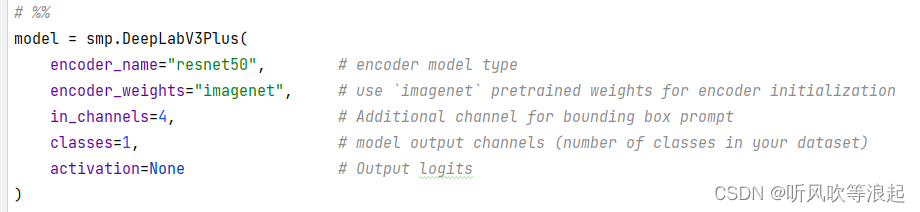

这里可以在deeplabv3代码体现:

bbox在数据上的表现就类似于画框,将图像指定区域框出来,所以输入的维度就多加了1

这里有个疑问,为什么对于医学的灰度图像,要repeat成3通道呢?

要不然输入应该是2,而非4了

其次,prompt 提示分割也可以借鉴,讲白了,就是把原始的rgb 3通道在加上一个通道,就是bbox的通道,这样每次unet的输入改成4就行了,也可以达到提示分割的目的。

dataset中对mask前景随机挑选一个,这样每次其实就是二分割任务,二分类任务简单不说,损失函数还可以实验BCE 逻辑损失。通过二分类的前景,取到bbox,增加到rgb图像中,这样输入就变成了4通道(这个思想可以添加到任何的分割网络中)